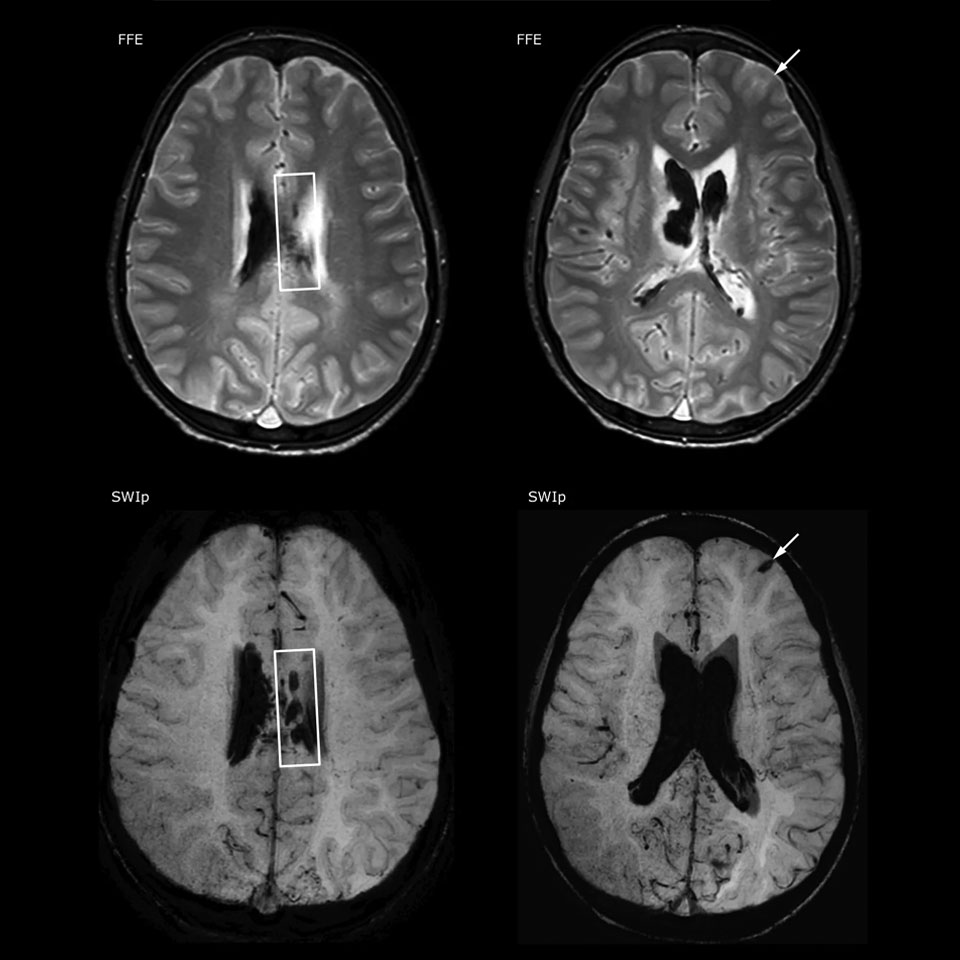

The value of susceptibility weighted imaging in visualizing brain injury is well documented. The Philips multi-echo SWIp technique provides fast susceptibility weighted imaging with enhanced susceptibility contrast and high resolution.

“Pediatric imaging is not without its challenges,” Dr. Miller says. “Since our patients are often very small, we need very high-resolution imaging. In cases of brain injury, we need to obtain information quickly so the treating clinicians can make decisions on care. We rely on high resolution and robust imaging capabilities, and SWIp provides that.”

“SWIp helps us identify blood or blood products, calcification, and diseases that affect the vascular system,” says Dr. Miller. “In children with traumatic brain injuries, it highlights areas that are injured, better than some of the previous techniques that we were using. These children often have micro-injuries that cause small amounts of blood or tissue damage. Adding SWIp helps us to better characterize the extent and nature of the injury. Having characterized an injury to the extent of what’s possible supports our diagnostic confidence.”

“I would definitely recommend other users to implement SWIp. We initially added the SWIp sequence following a lot of support for its utility in the literature. Then we directly compared SWIp to the 2D gradient echo sequences that we were using. After a good amount of clinical experience in seeing its benefits, we were confident to replace the old sequences with SWIp. It gives us a better assessment of the physiological processes of the brain that were less apparent on our previous imaging sequences,” says Dr. Miller. “SWIp is now a routine sequence for imaging traumatic brain injury patients at PCH, and it’s episodically added for patients who have intracranial vascular abnormalities.”